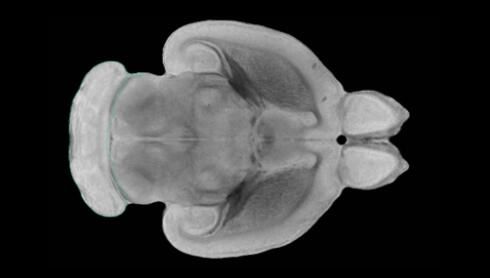

隨著機(jī)體年齡增加,肌肉和關(guān)節(jié)都會(huì)變得僵硬,這就會(huì)使得日?;顒?dòng)變得更加困難,本文研究表明,我們的大腦也是如此,與年齡相關(guān)的大腦僵硬對(duì)大腦干細(xì)胞的功能或許有著重要影響。文章中,研究人員對(duì)年輕和老化大鼠的大腦進(jìn)行研究闡明了年齡相關(guān)大腦僵硬對(duì)少突膠質(zhì)前體細(xì)胞(OPCs,oligodendrocyte progenitor cells)功能的影響。OPCs是一類對(duì)維持正常大腦功能非常重要的大腦干細(xì)胞,其對(duì)于髓磷脂的再生也非常重要,髓磷脂是神經(jīng)組織周圍的脂肪鞘,在多發(fā)性硬化癥中髓磷脂的再生常常會(huì)被損傷,機(jī)體老化對(duì)這些細(xì)胞的影響常常會(huì)誘發(fā)多發(fā)性硬化癥的發(fā)生,這些細(xì)胞的功能在老化的健康人群中同樣會(huì)下降。

為了確定老化OPCs的功能缺失是否可以被逆轉(zhuǎn),研究人員將來(lái)自老化大鼠機(jī)體的老化OPCs轉(zhuǎn)移到了年輕大鼠柔軟的海綿狀大腦組織中去,值得注意的是,這些老化的大腦細(xì)胞能夠重新恢復(fù)活力,其行為非常像年輕更加強(qiáng)壯的細(xì)胞。這項(xiàng)研究中,研究人員在實(shí)驗(yàn)室中開發(fā)出了具有可變僵硬程度的新型材料,并在受控環(huán)境下研究這些材料的生長(zhǎng)及其對(duì)大鼠大腦干細(xì)胞的影響,這些材料能被工程化改造具有和年齡或老化大腦相似的柔軟程度。